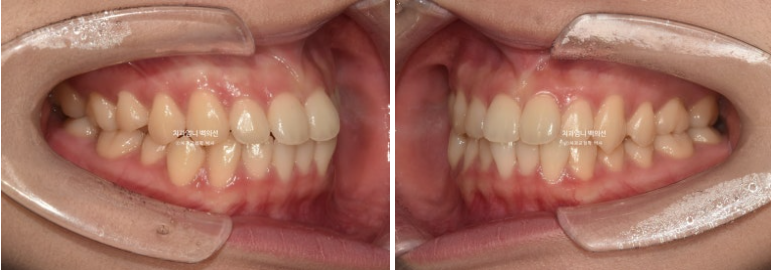

앞니가 뻗쳐 있습니다.

중심선이 처음에 비해 좋아졌으나 아직 불일치가 보입니다.

고무줄 처방으로 인해 중심선은 정확하게 맞으며

교합은 나쁘지 않습니다.

웃는 사진에서는 결손치 쪽으로 돌아가 있던 윗니 중심선이 드디어 코와 인중을 만나게 되었습니다.

그러나 왼쪽 앞니 하나가 미미하게 치축이 기울어져 보입니다.

중심선과 교합이 좋고 기울어진 앞니 하나의 치축도 개선이 되었습니다.

배열은 좋고

결손치 쪽으로 돌아가있던 상악 중심선은 아래중심선과도 만나게 되었습니다.